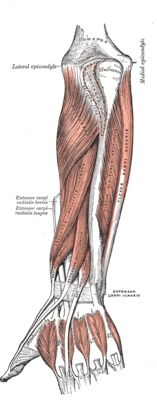

The forearm contains many muscles, including the flexors and extensors of the digits, a flexor of the elbow (brachioradialis), and pronators and supinators that turn the hand to face down or upwards, respectively. In cross-section the forearm can be divided into two fascial compartments. The posterior compartment contains the extensors of the hands, which are supplied by the radial nerve. The anterior compartment contains the flexors, and is mainly supplied by the median nerve. The ulnar nerve also runs the length of the forearm.

- "E/I" refers to "extrinsic" or "intrinsic". The intrinsic muscles of the forearm act on the forearm, meaning, across the elbow joint and the proximal and distal radioulnar joints (resulting in pronation or supination, whereas the extrinsic muscles act upon the hand and wrist. In most cases, the extrinsic anterior muscles are flexors, while the extrinsic posterior muscles are extensors.

- The brachioradialis, flexor of the forearm, is unusual in that it is located in the posterior compartment, but it is actually in the anterior portion of the forearm.

| Superficial muscles of the forearm |

| Deep muscles of the posterior forearm |